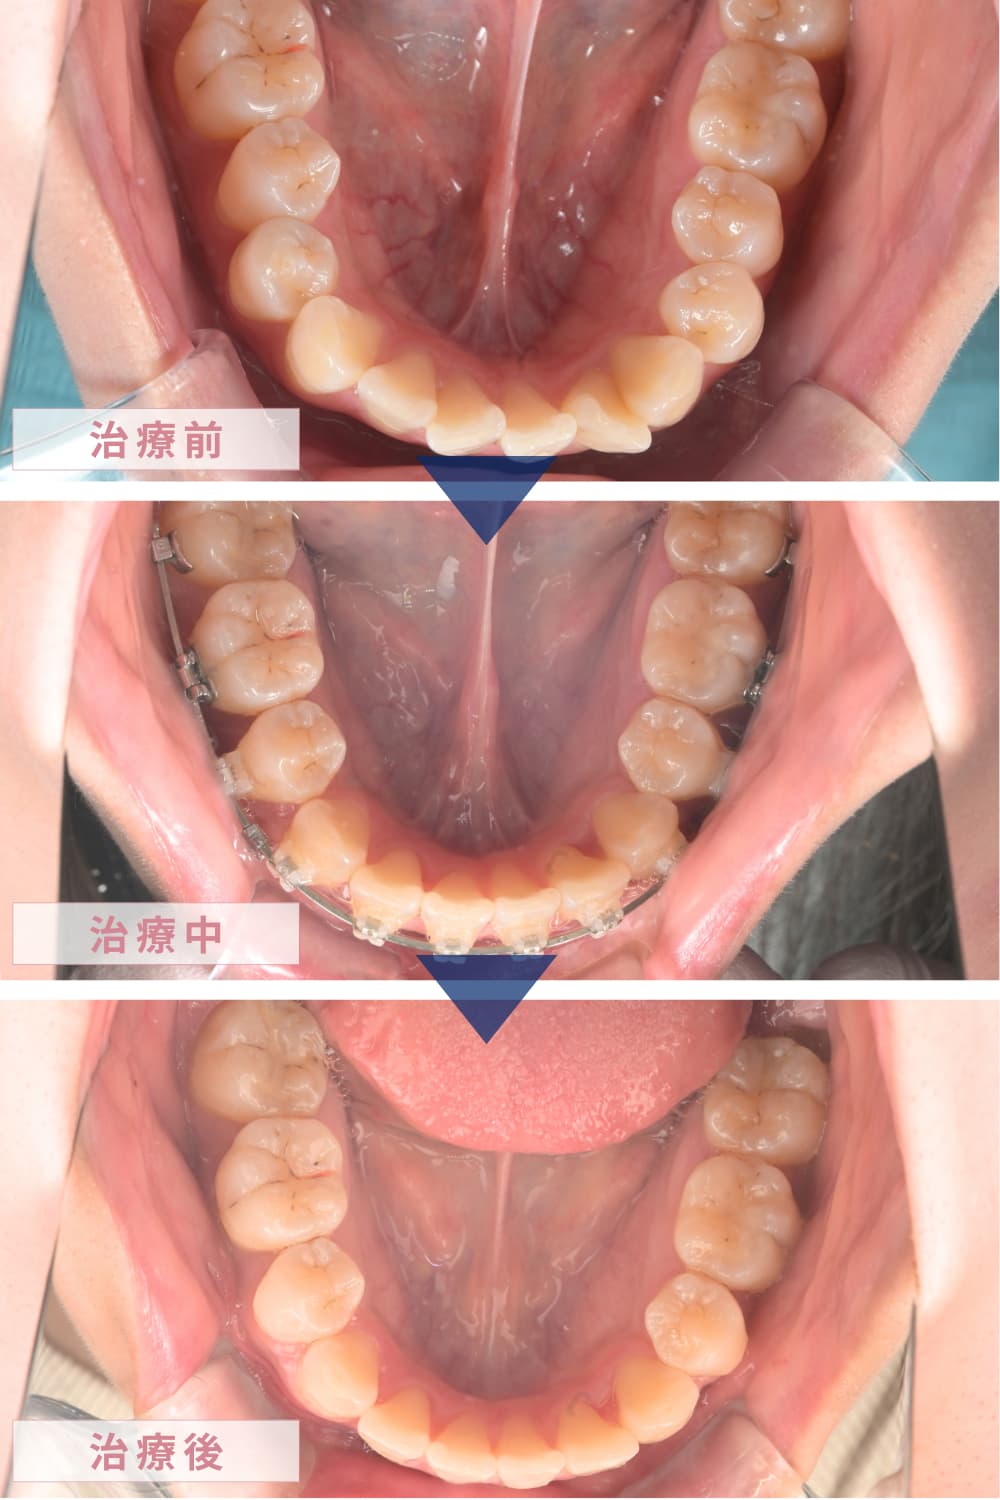

【治療経過画像】

《上顎》

《下顎》

約30回の通院を経て、動的治療(歯を動かす期間)が終了しました。

治療後は、ご本人の一番の悩みであった「口元の突出感」がなくなり、力を入れなくても自然に口が閉じられるようになりました。横顔のEラインも非常に美しく整い、コンプレックスが解消されたことで、患者さんの表情がとても明るくなられたのが印象的でした。